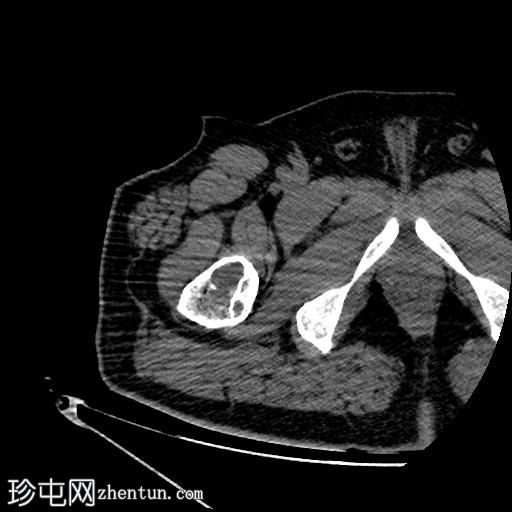

轴位骨窗

右股骨近端干骺端,股骨大转子下方可见一边界清晰的溶骨性病变。

未见皮质破坏及骨膜反应。